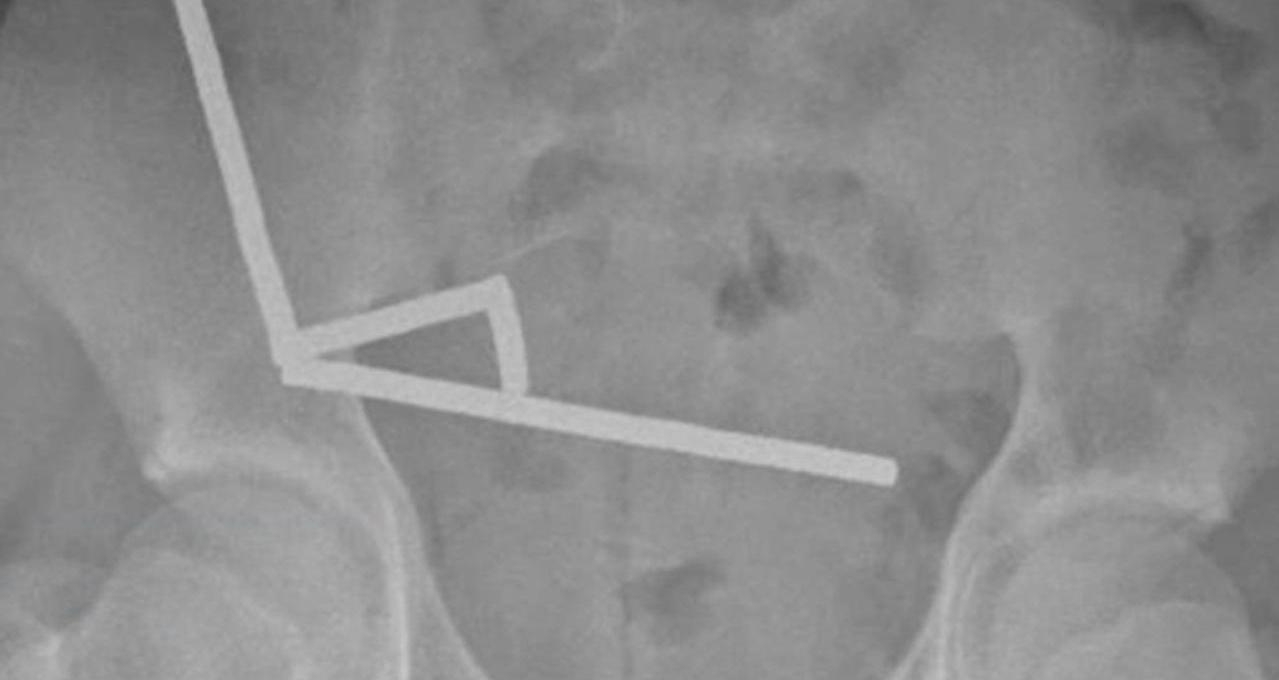

Na rendgenskim snimkama liječnici su ugledali četiri linearna lanca magneta raspoređena u različitim dijelovima crijeva. Njihova međusobna privlačnost uzrokovala je spajanje kroz tkivo, što je dovelo do prekida dotoka krvi i odumiranja dijelova crijeva.

Tijekom operacije liječnici su otkrili četiri spojena niza magneta u tankom crijevu i slijepom crijevu. Zbog oštećenja tkiva morali su kirurški ukloniti dio crijeva. Dječak se, prema izvješću, uspješno oporavio i otpušten je iz bolnice osam dana nakon operacije.